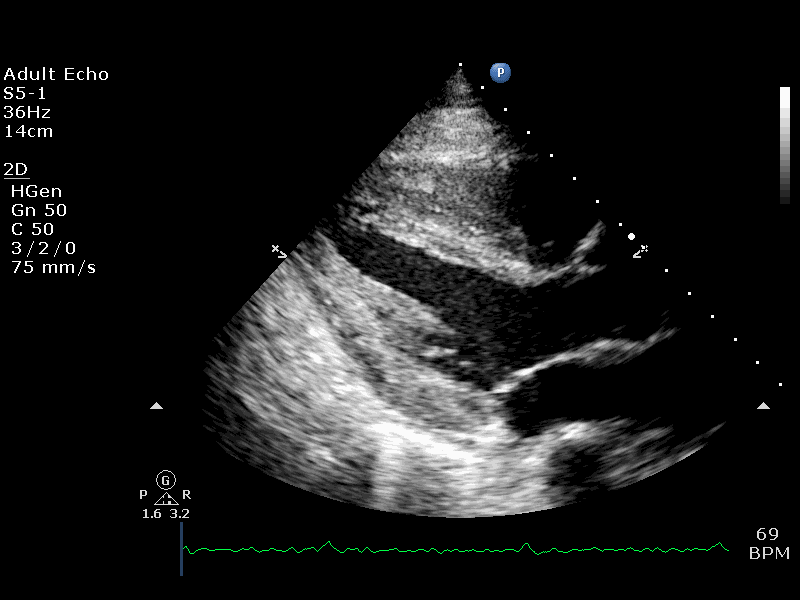

Visual Examples

PLAX Example 1 PLAX Example 2 PLAX Example 3 PLAX Example 4